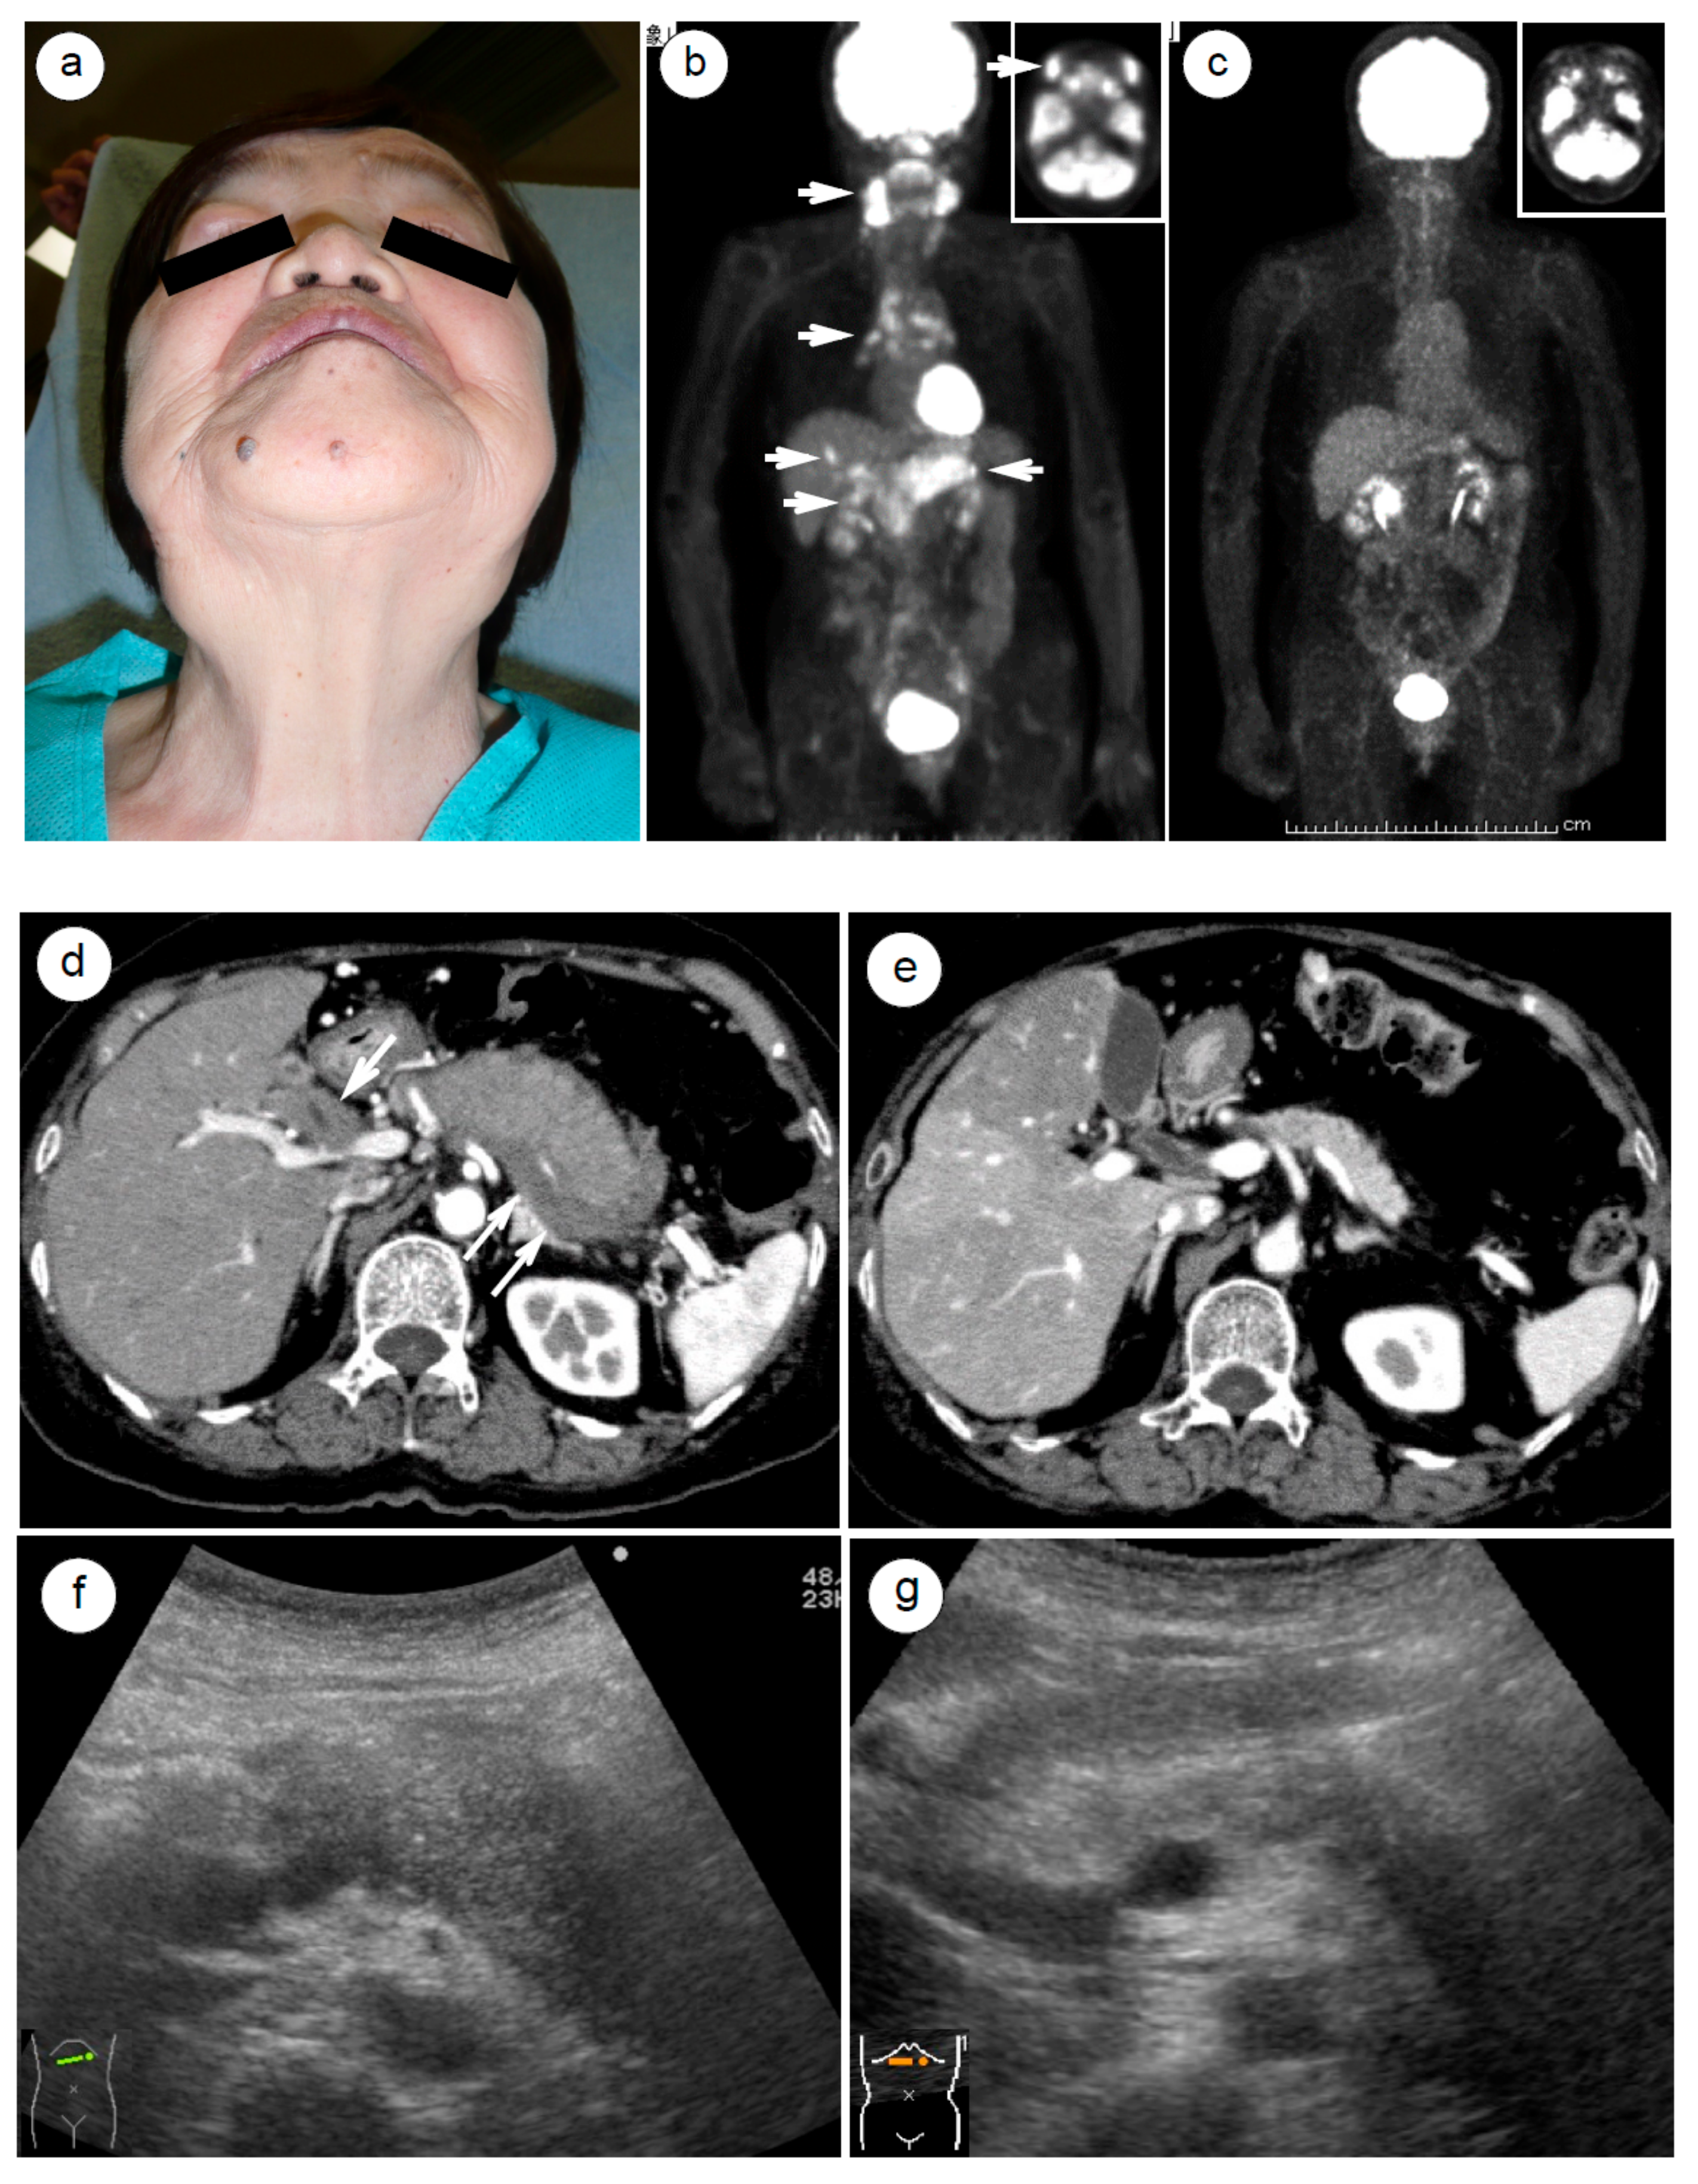

4.3. Radiological and Ultrasonographic Evaluation for Assessing AIP Response to Steroids

- Matsubayashi, H.; Yoneyama, M.; Nanri, K.; Sugimoto, S.; Shinjo, K.; Kakushima, N.; Tanaka, M.; Ito, S.; Takao, M.; Ono, H. Determination of steroid response by abdominal ultrasound in cases with autoimmune pancreatitis. Dig. Liver Dis. 2013, 45, 1034–1040. [Google Scholar] [CrossRef]

- Okabe, Y.; Ishida, Y.; Kaji, R.; Sugiyama, G.; Yasumoto, M.; Naito, Y.; Toyonaga, A.; Tsuruta, O.; Sata, M. Endoscopic ultrasonographic study of autoimmune pancreatitis and the effect of steroid therapy. J. Hepatobiliary Pancreat. Sci. 2012, 19, 266–273. [Google Scholar] [PubMed]